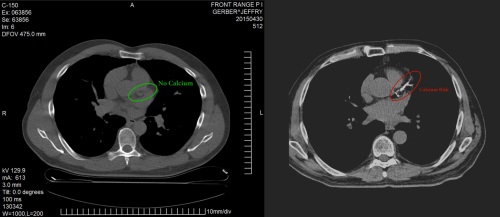

心臟電腦掃描是更先進的影像診斷檢查項目,而在心臟電腦掃描底下,可以再分為冠狀動脈鈣化定量(Calcium-score screening)及冠狀動脈造影(Coronary CT angiography, CTA)兩種。

3a. 冠狀動脈鈣化定量(Calcium-score screening)

冠狀動脈鈣化定量是一種非侵入性的檢查,用途是檢測冠狀動脈內的鈣化情況。如果動脈內出現鈣化,就會得到一個鈣化指數,醫生可依此來判斷動脈鈣化的嚴重程度,從而評估病人出現冠心病的機率,及早規劃進一步的預防方案。研究顯示,冠狀動脈血管狹窄程度與鈣化程度成正比,鈣化指數越高,冠狀動脈狹窄機率越高。

3b. 冠狀動脈造影(Coronary CT angiography, CTA)

冠狀動脈造影的原理,是利用高速多層螺旋電腦掃描器(Multiple detector computed tomography, MDCT)來掃描出多張心臟及心血管的橫切面圖片,然後拼砌出一個3D心臟影像,醫生就能準確診斷出早期冠狀動脈梗塞及心血管中極微量的鈣化現象,來評估患者出現冠心病的風險。

此項檢查進行前,醫生會透過導管將顯影劑注射到冠狀動脈的開口處,以便觀察冠狀動脈的狹窄程度,因此要由醫生臨床評估後,認為適合後才會進行。